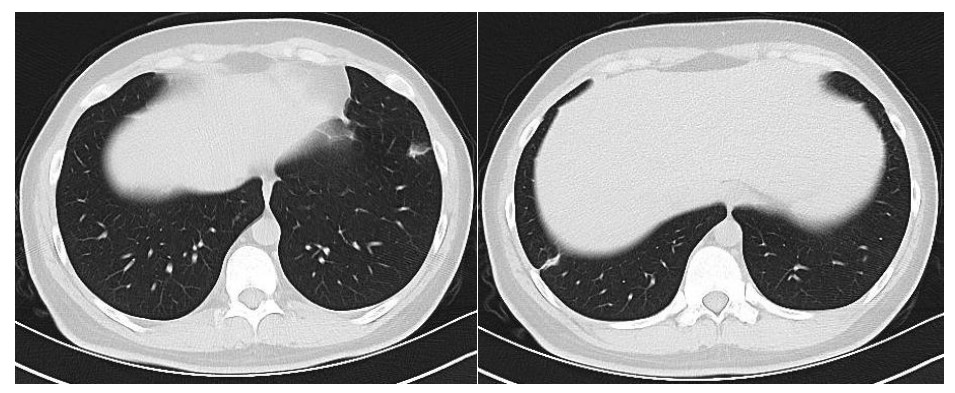

患者男性,21岁,主因“间断发热、寒战伴头晕头痛2周”于2021年11月18日急诊收入院。患者诉2周前进食烧烤后出现发热,体温最高可达42℃, 伴畏寒、寒战、咽痛、头晕、头痛、乏力,就诊于本院耳鼻喉科后,查体见扁桃体有脓点,快测降钙素原(procalcitonin,PCT)为37.27 ng/mL,胸部CT检查未见异常,考虑诊断为“急性化脓性扁桃体炎”,先后给予左氧氟沙星、阿奇霉素抗感染及甲泼尼龙控制炎症后上述症状未见明显好转,为进一步治疗,收入急诊病房治疗,既往体健,入院时查体:体温41℃,脉搏98次/min,呼吸频率23次/min,血压120/60 mmHg(1 mmHg=0.133 kPa),患者神志清楚,急性病容,精神较差,颈部浅表淋巴结触及肿大,右侧较大约2.0 cm ×0.5 cm,左侧较大约1.3 cm×0.7 cm,质软,活动度好,界限清楚,有压痛,表面皮肤无红肿,无破溃,双肺呼吸音清,未闻及干湿性啰音,心脏听诊无杂音,腹软,无压痛及反跳痛,双下肢无水肿。血常规检查白细胞计数10.49×109/L, 中性粒细胞百分比94.6%,血红蛋白120 g/L, 血小板计数107×109/L,PCT 42.83 ng/mL,白介素6(interleukin, IL-6)980.30 pg/mL,C反应蛋白211 mg/L,G试验、GM试验阴性。胸部CT检查示右肺上叶可见一单发实变影,其内可见空洞(图 1)。根据病史、查体和辅助检查考虑诊断为肺脓肿,给予注射用哌拉西林钠他唑巴坦4.5 g Q8h治疗,入院第2天,患者仍有发热,体温最高38.7℃,给予对症处理,入院第3天患者体温峰值有所下降,体温维持在37~38℃,考虑抗炎有效,痰培养结果回报为纹带棒杆菌,草绿色链球菌(奈瑟菌属),考虑这2种细菌为皮肤或口腔的正常菌群,为条件致病菌,该细菌导致发热的可能性较小,继续给予哌拉西林钠他唑巴坦治疗。入院第5天血培养回报血液中找到坏死梭杆菌,考虑为血流感染。加用甲硝唑1 g每8 h一次抗感染治疗,复查血常规白细胞计数8.14×109/L, 中性粒细胞百分比81.5%,血红蛋白120 g/L, 血小板计数246×109/L,PCT 3.43 ng/mL,IL-6 13.04 pg/mL,C反应蛋白5 mg/L,炎性指标较前明显下降,考虑抗炎治疗有效,继续目前抗生素治疗。入院第10天患者体温仍有低热,体温36.5~37.5 ℃,复查胸部CT见双肺多发小结节,双肺多发空洞病变,考虑炎性可能(图 2)。颈静脉超声检查提示患者左侧颈内静脉血栓形成,给予依诺肝素0.4 mL每12 h一次抗凝治疗,根据血培养结果、胸部CT表现和颈静脉超声结果,考虑该患者诊断为坏死梭杆菌导致Lemierre综合征(Lemierre syndrome, LS)。用哌拉西林钠他唑巴坦联合甲硝唑治疗后仍有低热,化验检查PCT为0.30 ng/mL,IL-6为3.52 pg/mL,C反应蛋白为3 mg/L,胸部CT示肺部空洞较前增加,考虑感染未完全控制,改为调整抗生素为比阿培南0.6 g每12 h一次联合甲硝唑1g每8 h一次抗感染治疗,治疗1周后患者体温恢复正常,CT检查示双肺多发空洞消失,残留少量索条影(图 3),患者病情好转出院,出院带药给予口服甲硝唑联合阿莫西林抗感染治疗,利伐沙班抗凝治疗,随诊2周后复查胸部CT正常。

| 空洞病变消失,残留少量实变及索条影 图 3 入院第19天胸部CT |

LS的致病菌主要为坏死梭杆菌,因此LS也被称为坏死梭杆菌病,其他致病菌包括核杆菌、类杆菌、链球菌和葡萄球菌等[5]。坏死梭杆菌为厌氧革兰阴性多形态杆菌,广泛存在于人类和动物的口腔、上呼吸道、胃肠道和泌尿生殖道的正常菌群。坏死梭杆菌可以产生白细胞毒素、内毒素、溶血素和血细胞凝集素等,白细胞毒素和溶血素与脓肿形成相关,血细胞血凝素可引起动静脉血栓形成,可导致转移性脓肿,弥漫性血管内凝血和血小板减少也与此有关[6]。患者起初为咽部感染,然后通过咽旁间隙侵袭至颈内静脉,形成颈内静脉血栓,脓毒性栓子随着血流播散至肺部,引起肺部脓肿和肺栓塞。本例患者刚发热时胸部CT正常,门诊给予喹诺酮类药物和大环内酯类药物治疗2周后,入院时胸部CT示患者右肺中叶单发实变影,其内可见空洞样变,后随病情发展,胸部CT示双肺多发肺空洞样变,符合LS的临床表现。LS最初表现为喉咙痛或颈部疼痛, 但可出现多种非特异性症状, 如全身僵硬、寒战、发热、颈部淋巴结肿大、眼眶疼痛、骨/关节疼痛、四肢无力、恶心、呕吐等胃肠道症状。最初感染1周后,可以在血液中找到细菌,然后在颈静脉内脓毒性血栓形成,可以肺内形成肺脓肿和脓胸,也可以累及关节[7]。